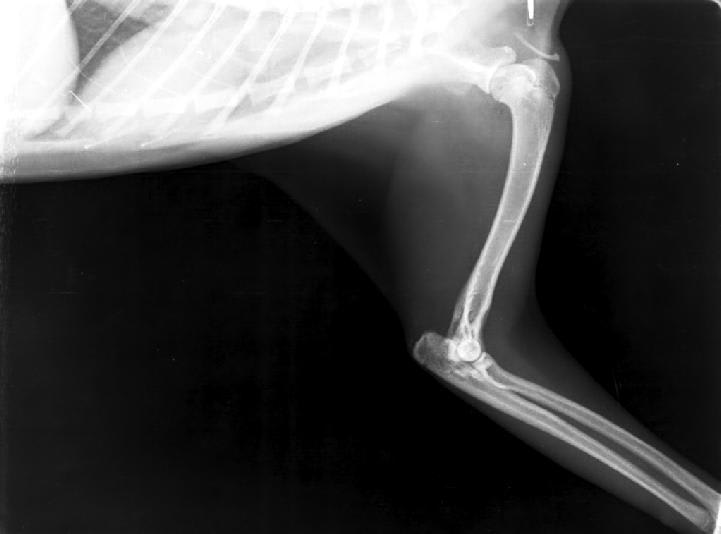

My kitten is one year old, she has calicivirus and has been diagnosed with osteoarthritis. These are hers x-rays. My vet doesn't want to operate. I don't know what to do. Sorry for my grammar mistakes, I am not native english.

Hello, sorry to hear about Kairi. It sounds like besides her calicivirus, she is having some difficult time walking? If so, it is believed that this is secondary to osteoarthritis. Young cats with osteoarthritis can often have more than one joint affected and is often something that is management medically. Finding the underlying cause for this osteoarthritis such as infection, an inflammatory response, auto-immune disease, or an old injury must be determined. Surgery may not be able to treat the osteoarthritis but rather help her walk easier. Surgical intervention is often pursued as a salvage procedure and not before diagnosing the source of the osteoarthritis and its effect. I would recommend asking your veterinarian to refer Kairi to an orthopedic surgeon so that they may evaluate her and determine if one or more joints are affected and if surgery or medical management is best for her. Hope this helps and best of luck.